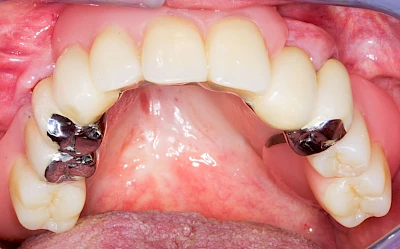

Auch wenn Zahnprothesen drücken, sollten vor allem Teilprothesen jeden Tag wenigstens für ein paar Minuten getragen werden, damit sich die eigenen Zähne nicht unbeabsichtigt verstellen und die Prothese weiter passt.

Aber Achtung: Manche Menschen fühlen sich ohne Zahnprothesen unwohl. Zudem kann es passieren, dass Zahnprothesen (wenn noch eigene Zähne vorhanden sind) nicht mehr passen. Dies gilt vor allem dann, wenn diese Zahnprothesen nicht nur über Nacht, sondern für einen längeren Zeitraum nicht mehr getragen werden.